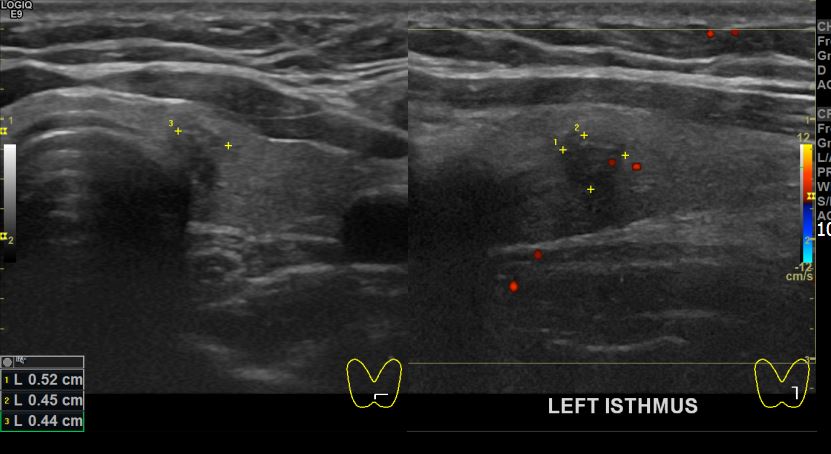

상기환자 검진이상으로 내원하신 30대중반 여성분으로 좌엽 의심스러운혹 세포검사진행후 갑상선암으로 진단되었습니다